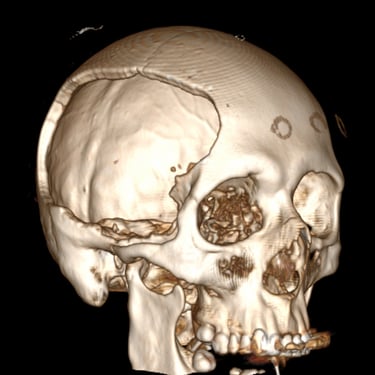

TEC Severo: Craneotomía Descompresiva Hemisférica y Evacuación de Hematoma Extradural

El traumatismo encéfalo craneano (TEC) severo es una emergencia neurológica que puede comprometer rápidamente la vida del paciente. Cuando existe edema cerebral difuso y hematomas asociados, el tratamiento quirúrgico oportuno es fundamental. La craneotomía descompresiva hemisférica derecha permite reducir la presión intracraneal y prevenir daño cerebral secundario, mientras que la craneotomía temporal izquierda con evacuación de hematoma extradural (HED) elimina el efecto de masa local. Este abordaje combinado busca preservar la perfusión cerebral, estabilizar al paciente y mejorar el pronóstico neurológico en situaciones críticas.